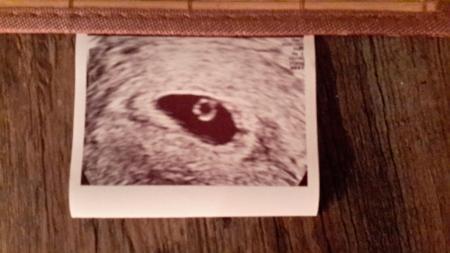

Hallo, Das ist mein Bild aus der 1. SS von 5+1. Habe am Freitag Termin, bin da 5+2 und ich weiß dass man wahrscheinlich auch nich mehr sehen wird, aber mein FA möchte mich immer zeitig sehen um ne ELSS etc rechtzeitig zu erkennen bzw auszuschließen.. Lg

Ich war bei 5+5 beim FA und man hat alles ganz deutlich gesehen. Das Herz hat sogar auch schon geschlagen -FA meinte aber, dass dies wohl der erste Tag sein muss. :) hänge das Bid mal an.